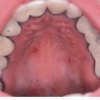

Ancyloglossia

Kaasasündinud anomaalia, mille juures keel on tugevalt fikseerunud suupõhjas. Selline anomaalia oluliselt ei takista rääkimist, kuid takistab loomulikku suuõõne (hambad, suuesik) puhastumist keele abil ja foneetikat. Keelekida haavandumine tekib pideva...